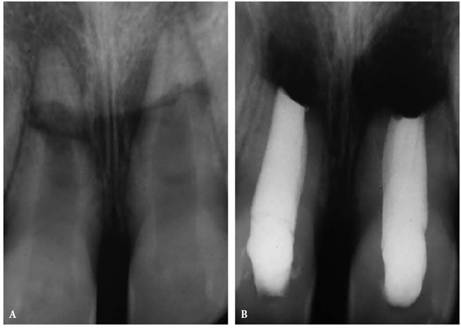

In most cases, an endodontic procedure should not be initiated without

evaluating at least two recent radiographs exposed at different horizontal

angulations of the suspected tooth (Figures 19-24A

and B).

Comparing varied views is essential in diagnosing the presence of additional

roots, anatomic configurations, anomalies, and other unusual circumstances that

may complicate the treatment.

Figure 19-24A and B: (A) Pretreatment radiograph of a mandibular premolar shows one canal. (B) A second radiograph taken from an angulation of 15 degrees from the mesial discloses a second root.